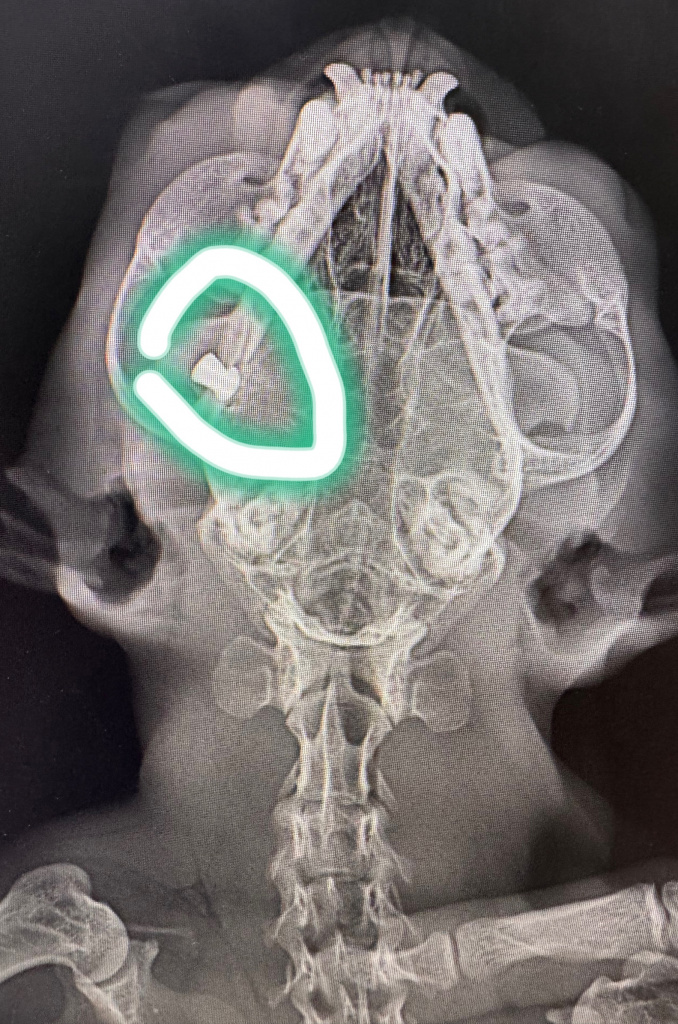

В паблике клинике в социальных сетях написано, что пушистик поступил к врачам с травмой глаза. Рентгеновский снимок показал, что в кошачьем черепе застряла пуля.

Врачи не знают, кто стрелял; целились в голову. Бедолаге сделали экстренную операцию - энуклеацию глазного яблока. Как известно, у котов девять жизней: несчастный выжил, но остался инвалидом.

«К сожалению, пулю не удалось достать, так как она располагалась очень глубоко и останется с ним навсегда», - констатировали врачи.